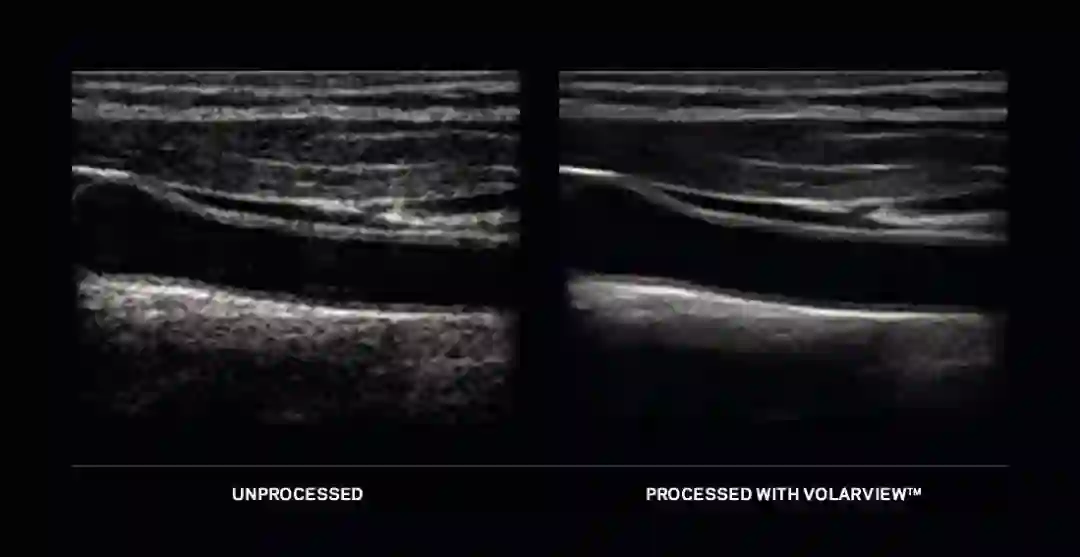

自1983年起,康泰瑞影就为世界医疗影像界提供领先的影像增强软件解决方案,并不断推出全新的软件和专有技术。近日,康泰瑞影在今年的中国国际医疗器械博览会(CMEF)上展出两款全新产品:用于手持超声设备的VolarView™以及用于X光成像的骨科套件。

超声技术没有电磁波辐射,比较安全,设备可应用于各种场合,操作简单。随着手持设备可用性的增加,超声应用已超越传统范围,应用领域和用户变得更为广泛。VolarView™是康泰瑞影推出的可在手机和平板等各类手持设备上使用的解决方案,代表康泰瑞影已经能够为全类别超声系统提供智能影像增强技术,以满足日益增加的照料病患的需求。